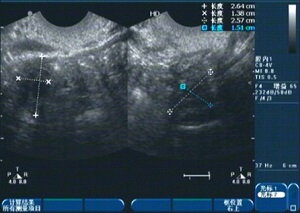

1、診斷:醫(yī)生會通過詢問病史、體檢及輔助檢查(如超聲檢查、激素檢測等)來確定診斷。